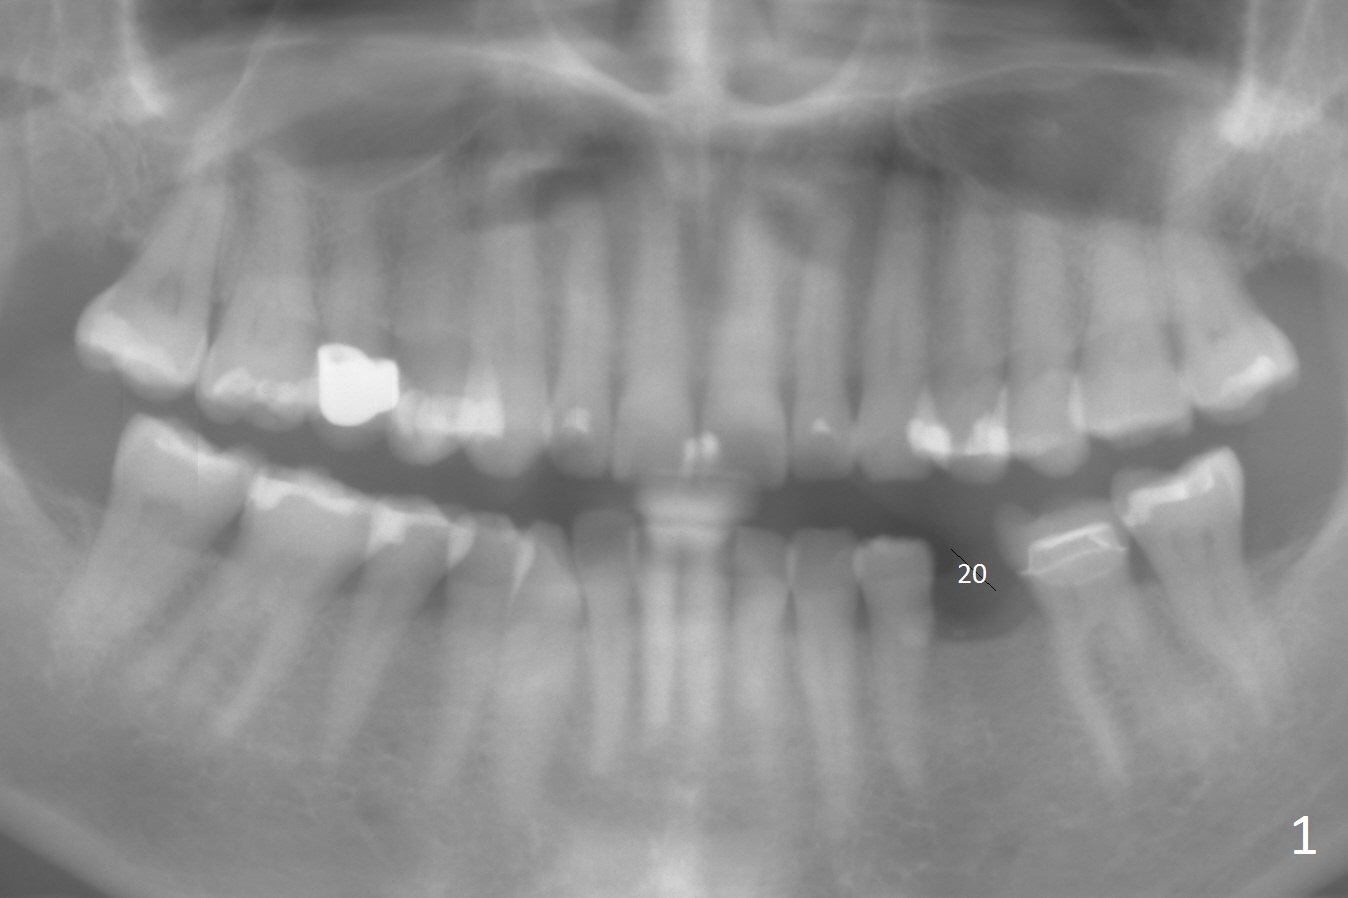

A 54-year-old woman has good oral hygiene. Panoramic X-ray shows generalized long roots, which suggest bruxism (Fig.1). Since the bone height is sufficient, a long implant will be placed, probably 4x13 mm (Fig.2). Take photos of the edentulous space, concentrating on the ridge top. Flap surgery will be performed. Crestal bone is going to be reduced if the ridge is narrow. PA is taken after 1.6 mm drill for 11 mm. If the trajectory is correct, a 3.3 mm Magic Drill is to be used (13 mm stopper, after Marking bur), followed by 4x11 mm dummy implant. If the bone is dense, a final drill will be used for 14 mm before placement of the definitive implant. The harvested autogenous bone will be placed around a pair abutment to increase the buccolingual width. Take postop photos to show the ridge augmentation.